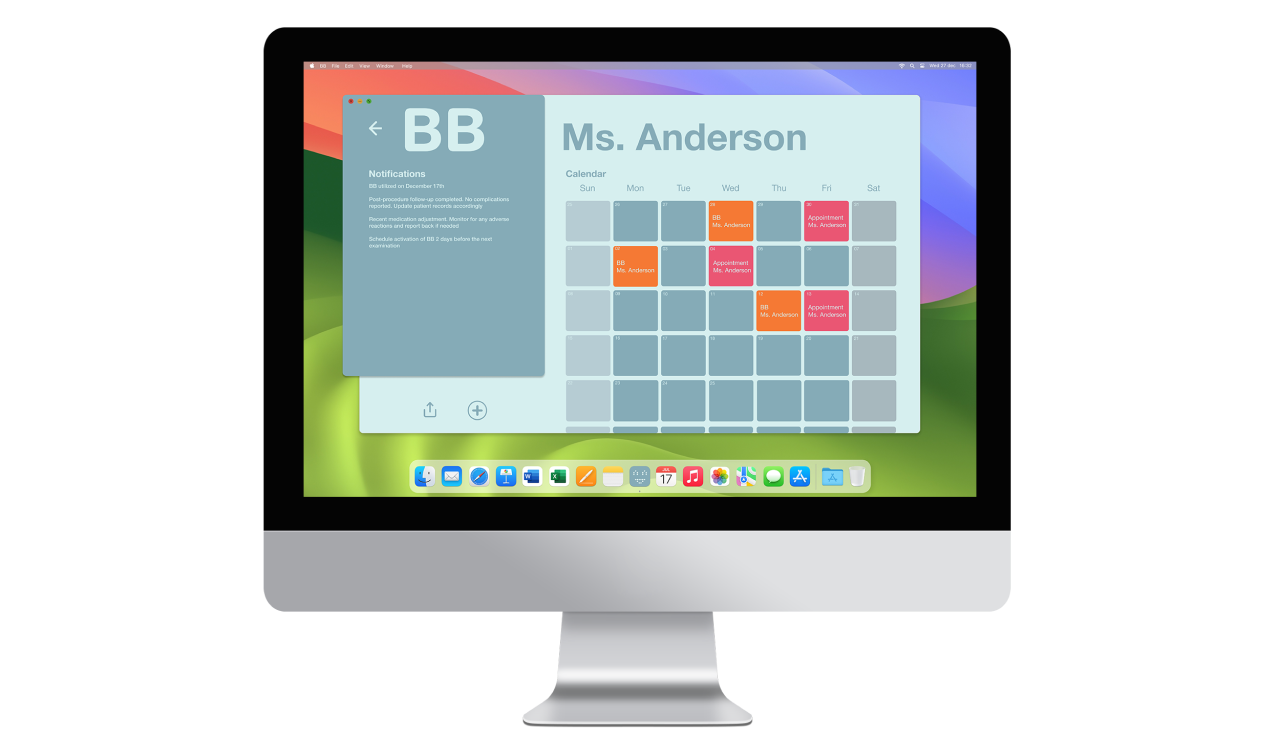

(2) B-B [product-service system for pregnancy monitoring]

B-B is a product-service system that connects pregnant women with their gynecologists through a monitoring device that tracks key health parameters while strengthening the emotional bond with the unborn child. It fosters closer relationships and more holistic, emotionally connected prenatal care.

The gynecologist’s user experience prioritizes minimal invasiveness and comfort, incorporating alert notifications for irregularities during monitoring. Additionally, a desktop interface allows access to data reports and appointments, benefiting both gynecologists and administrative staff. Administrative access enables efficient scheduling of device activations, enhancing coordination within the healthcare system.